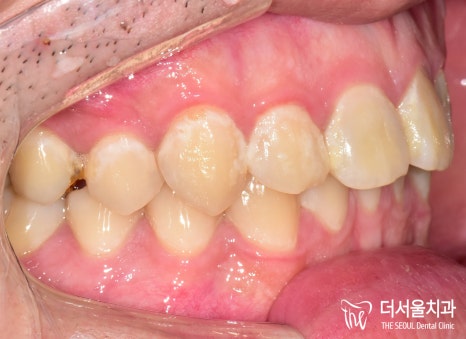

그런데 문제는 정면이 아닌 옆이었는데요.

왼쪽에 작은 어금니 하나가 비었죠?

25번 어금니를 상실해 있습니다.

교합면을보면 뭔가 좁다는 느낌을 받을 수 있는데,

치아를 상실한지 조금 오래 되었다 하셨습니다.

그래서 25번 위치는 픽스처를 식립하기

힘든 상태였습니다.